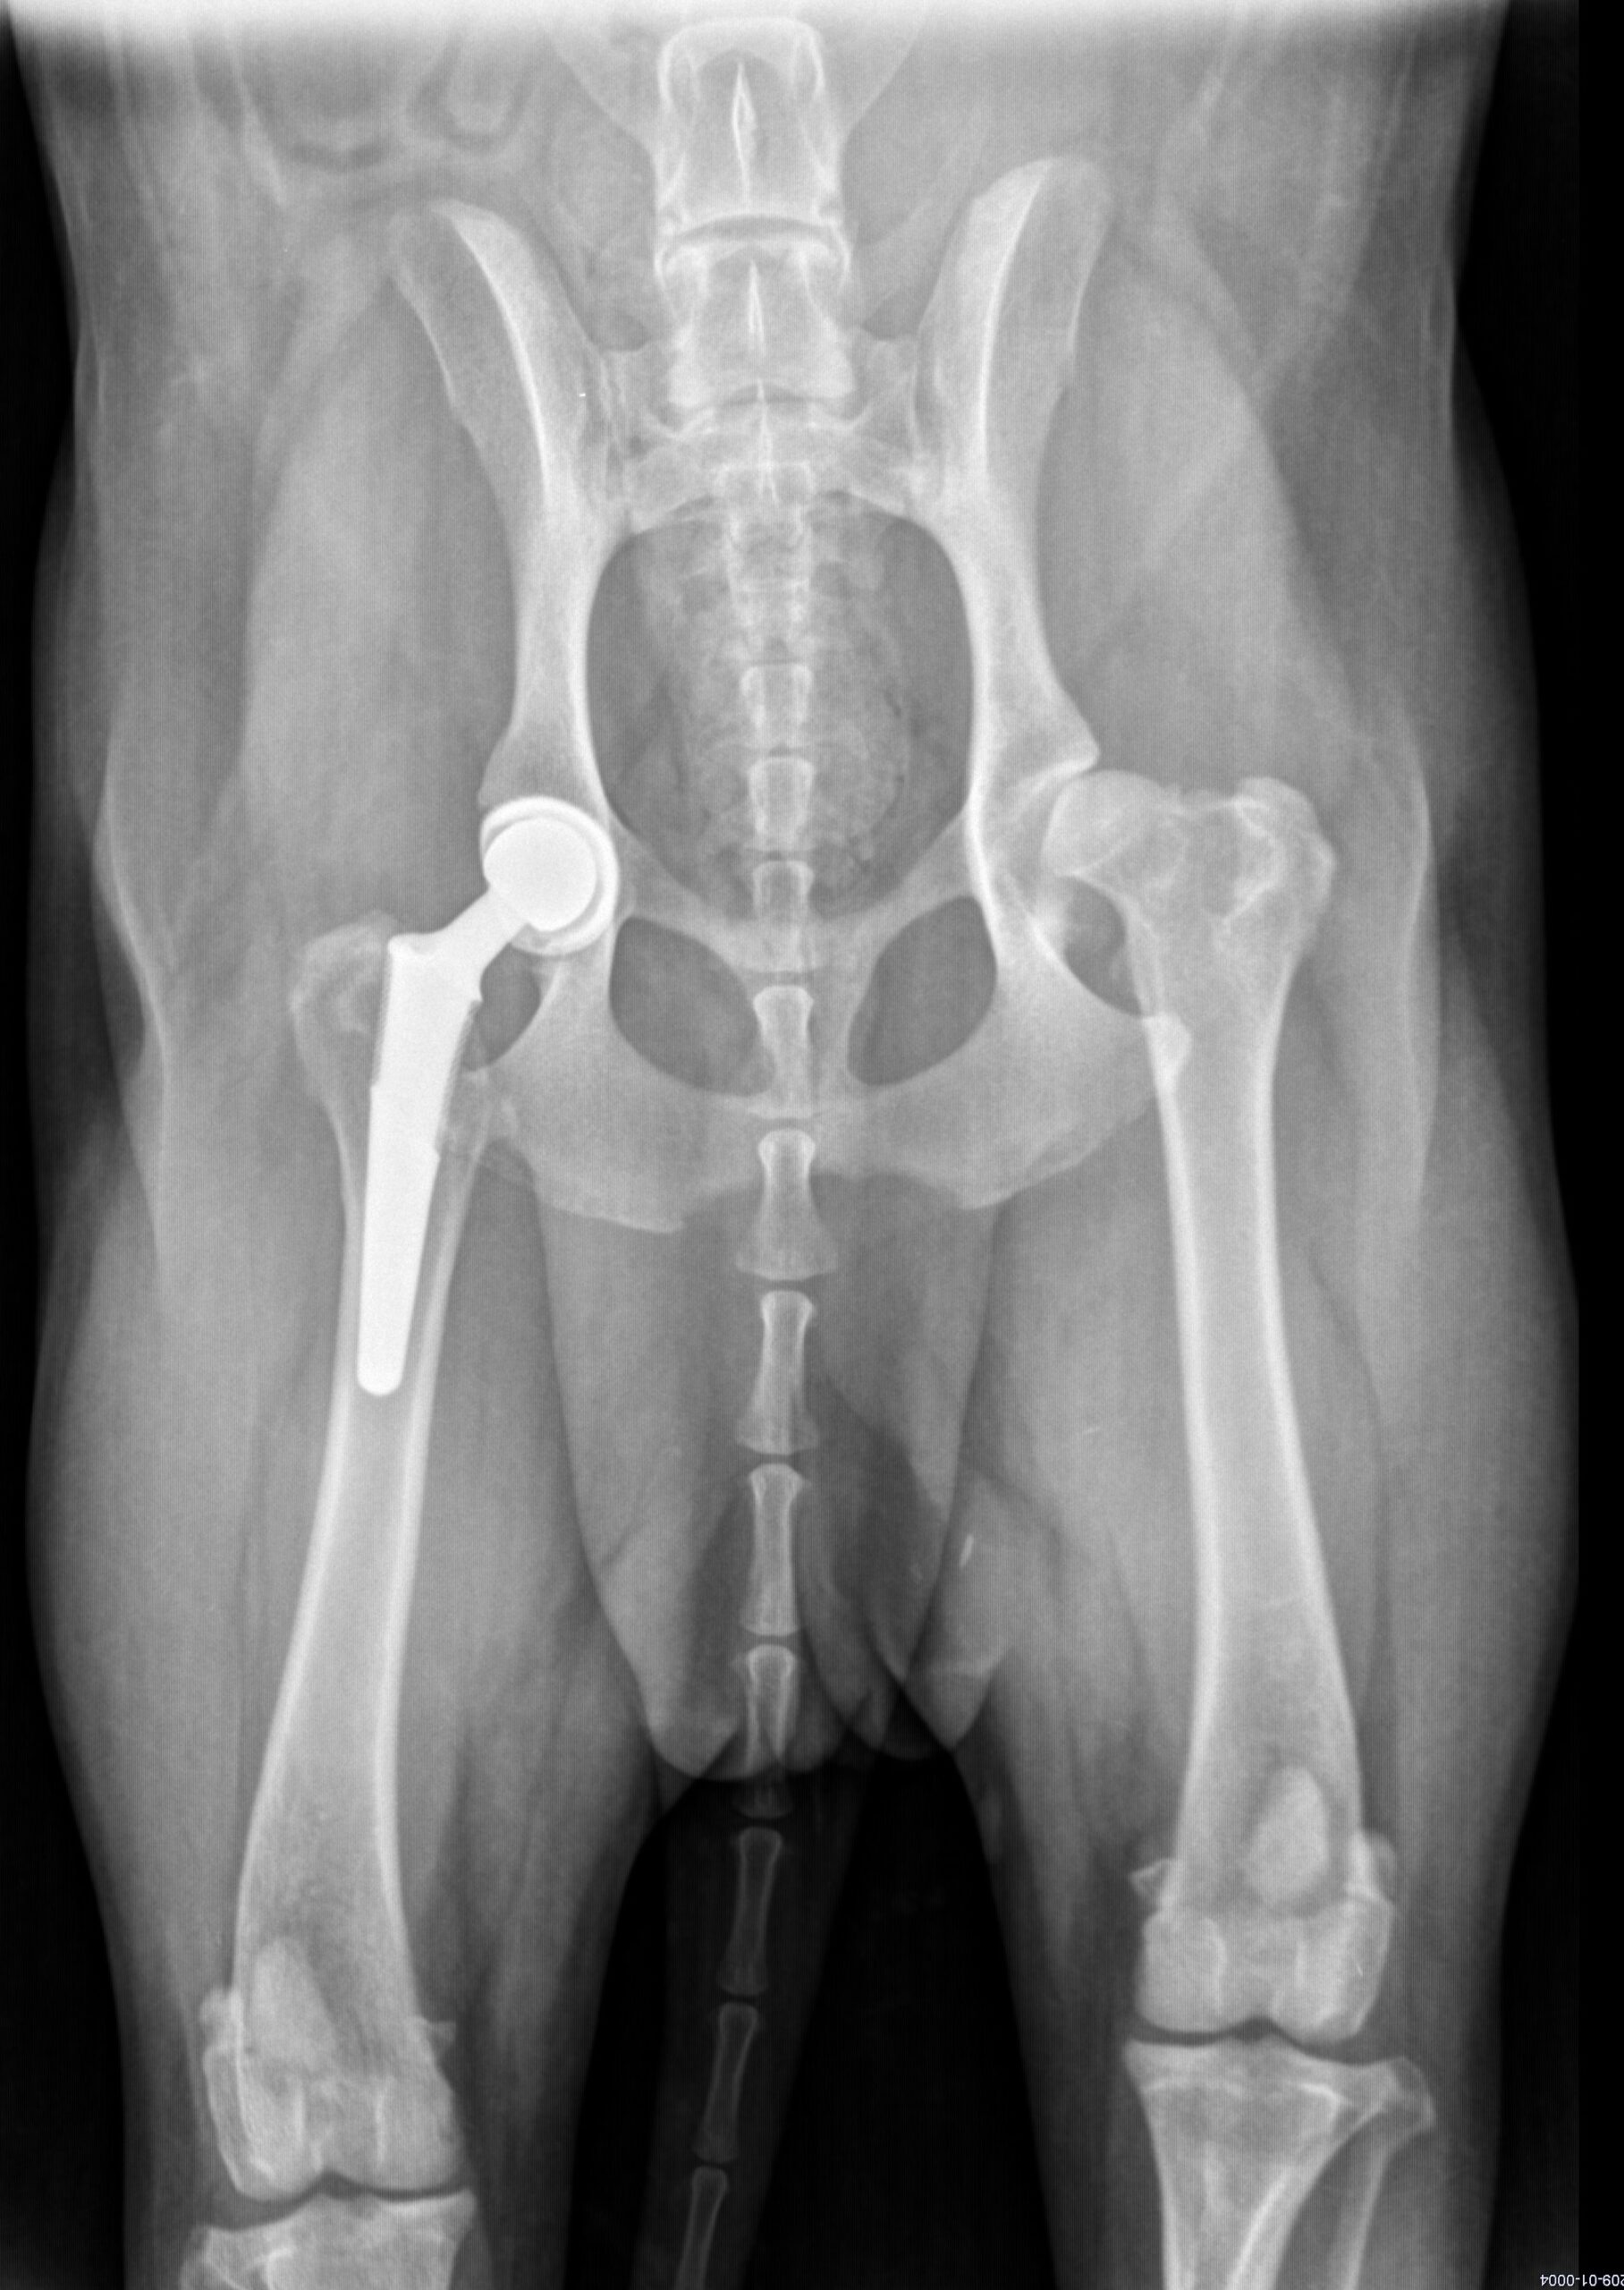

Dysplasie de la hanche chez le chien